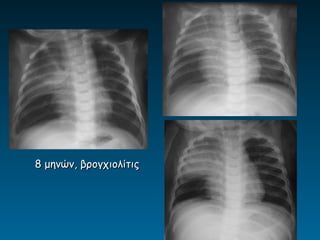

8 μηνών, βρογχιολίτις

βρογχιολίτιδα

ασθματική κρίση